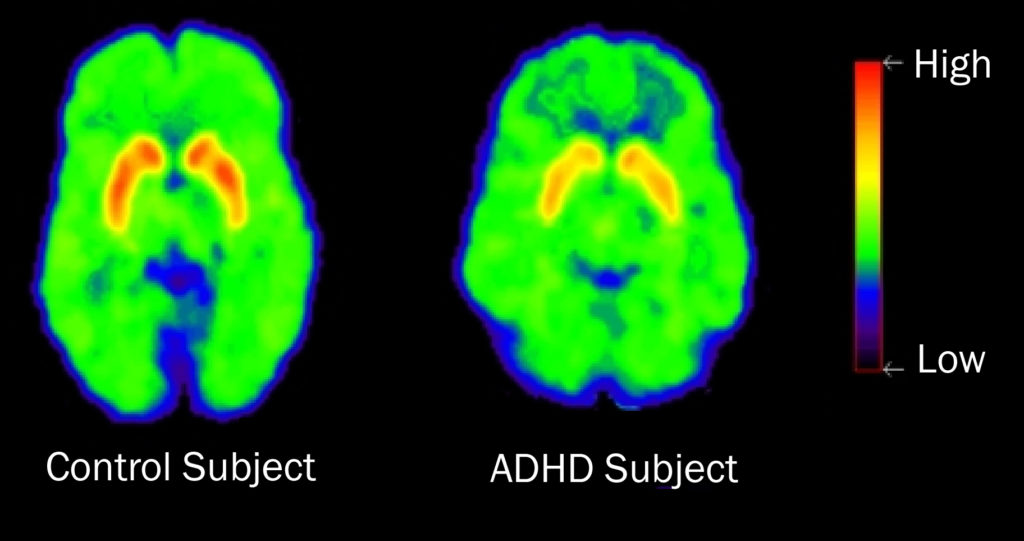

ADHD Brain Vs Normal Brain Functions Differences More

ADHD Brain Differences Stuff4Educators

ADHD Is A Dopamine Disorder Not A Learning Disability Trans Icarus

Compare Normal Vs ADHD Brain YouTube